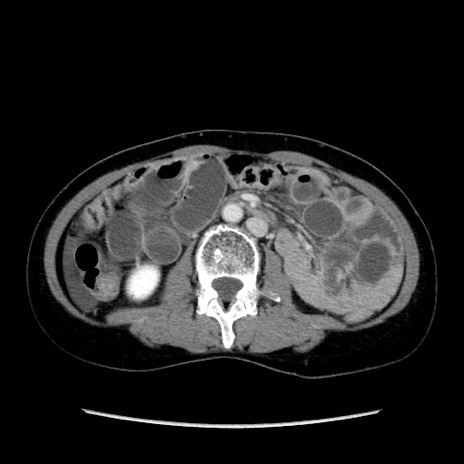

症例32(横断像)

【症例】40歳代 女性

【主訴】上腹部痛、嘔気・嘔吐

【現病歴】約9時間前頃から急に上腹部痛、嘔気、嘔吐が出現。改善しないため救急要請。

【既往歴】子宮頚癌(広汎子宮全摘術、放射線療法)、腸閉塞

【身体所見】腹部:平坦、軟、腸雑音亢進、上腹部を中心に腹部全体に圧痛あり。

【データ】WBC 8400、CRP 0.03